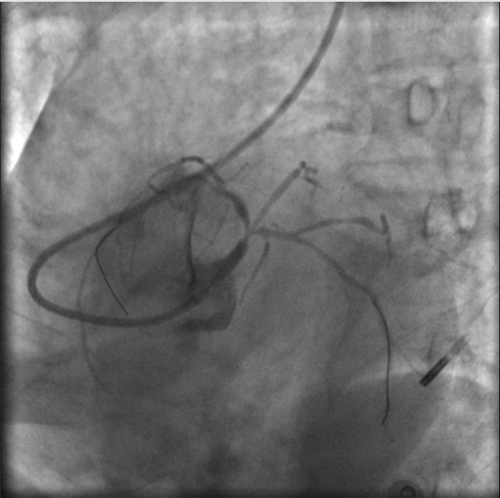

右側(cè)肱動脈重度狹窄

快速完成右側(cè)橈動脈穿刺,上造影導(dǎo)管受阻后,行肱動脈造影,發(fā)現(xiàn)右側(cè)肱動脈重度狹窄。

左主干完全閉塞

小心操作導(dǎo)絲及導(dǎo)管,艱難到達(dá)主動脈根部,但導(dǎo)管難以“到位”左冠口,“冒煙”見左主干居然完全閉塞了。

右冠近段嚴(yán)重狹窄,未見右向左的側(cè)枝循環(huán)

再行右冠造影,右冠近段也嚴(yán)重狹窄,未見右冠向左冠的側(cè)枝循環(huán)。

IABP(主動脈內(nèi)球囊反搏)

突發(fā)的狀況并沒有打亂團(tuán)隊的陣腳,待生命體征穩(wěn)定后,決定先植入IABP(主動脈內(nèi)球囊反搏)提供循環(huán)支持,防止病情進(jìn)一步惡化。穿刺雙側(cè)股動脈,分別置入IABP導(dǎo)管及左冠指引導(dǎo)管。

因患者股動脈扭曲,導(dǎo)管操控困難,術(shù)者反復(fù)嘗試,以導(dǎo)絲飄進(jìn)左主干,在球囊的支撐下,通過閉塞段到達(dá)中間支,小壓力擴張后造影可見主干末端嚴(yán)重狹窄。隨后小心操控導(dǎo)絲到達(dá)回旋支、前降支,送入球囊擴張,嚴(yán)重狹窄的左主干末端被撐開,左冠血流終于恢復(fù),胡女士暫時轉(zhuǎn)危為安。

球囊擴張后,左冠血流恢復(fù),但左主干末端重度狹窄